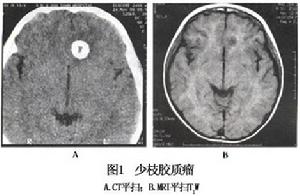

2.CT掃描 多呈低密度占位影像90%的腫瘤內有高密度鈣化區時常在腫瘤周邊部。非鈣化部分表現為等、低密度影,增強後有時有強化。

3.MRI掃描 腫瘤T1加權像呈低信號,T2加權像為高信號,周圍水腫易與腫瘤相區分若腫瘤有較大的鈣化MRI呈低信號區。少枝膠質細胞瘤注藥後的對比增強比較突出。